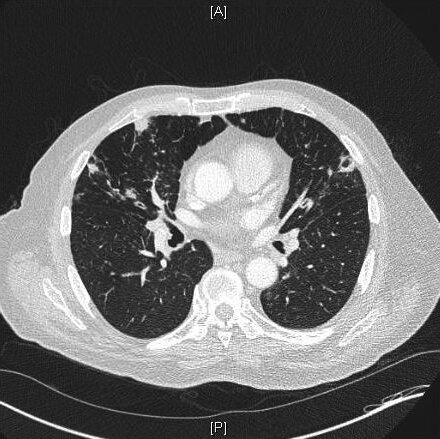

most likely diagnosis:

bronchiectasis